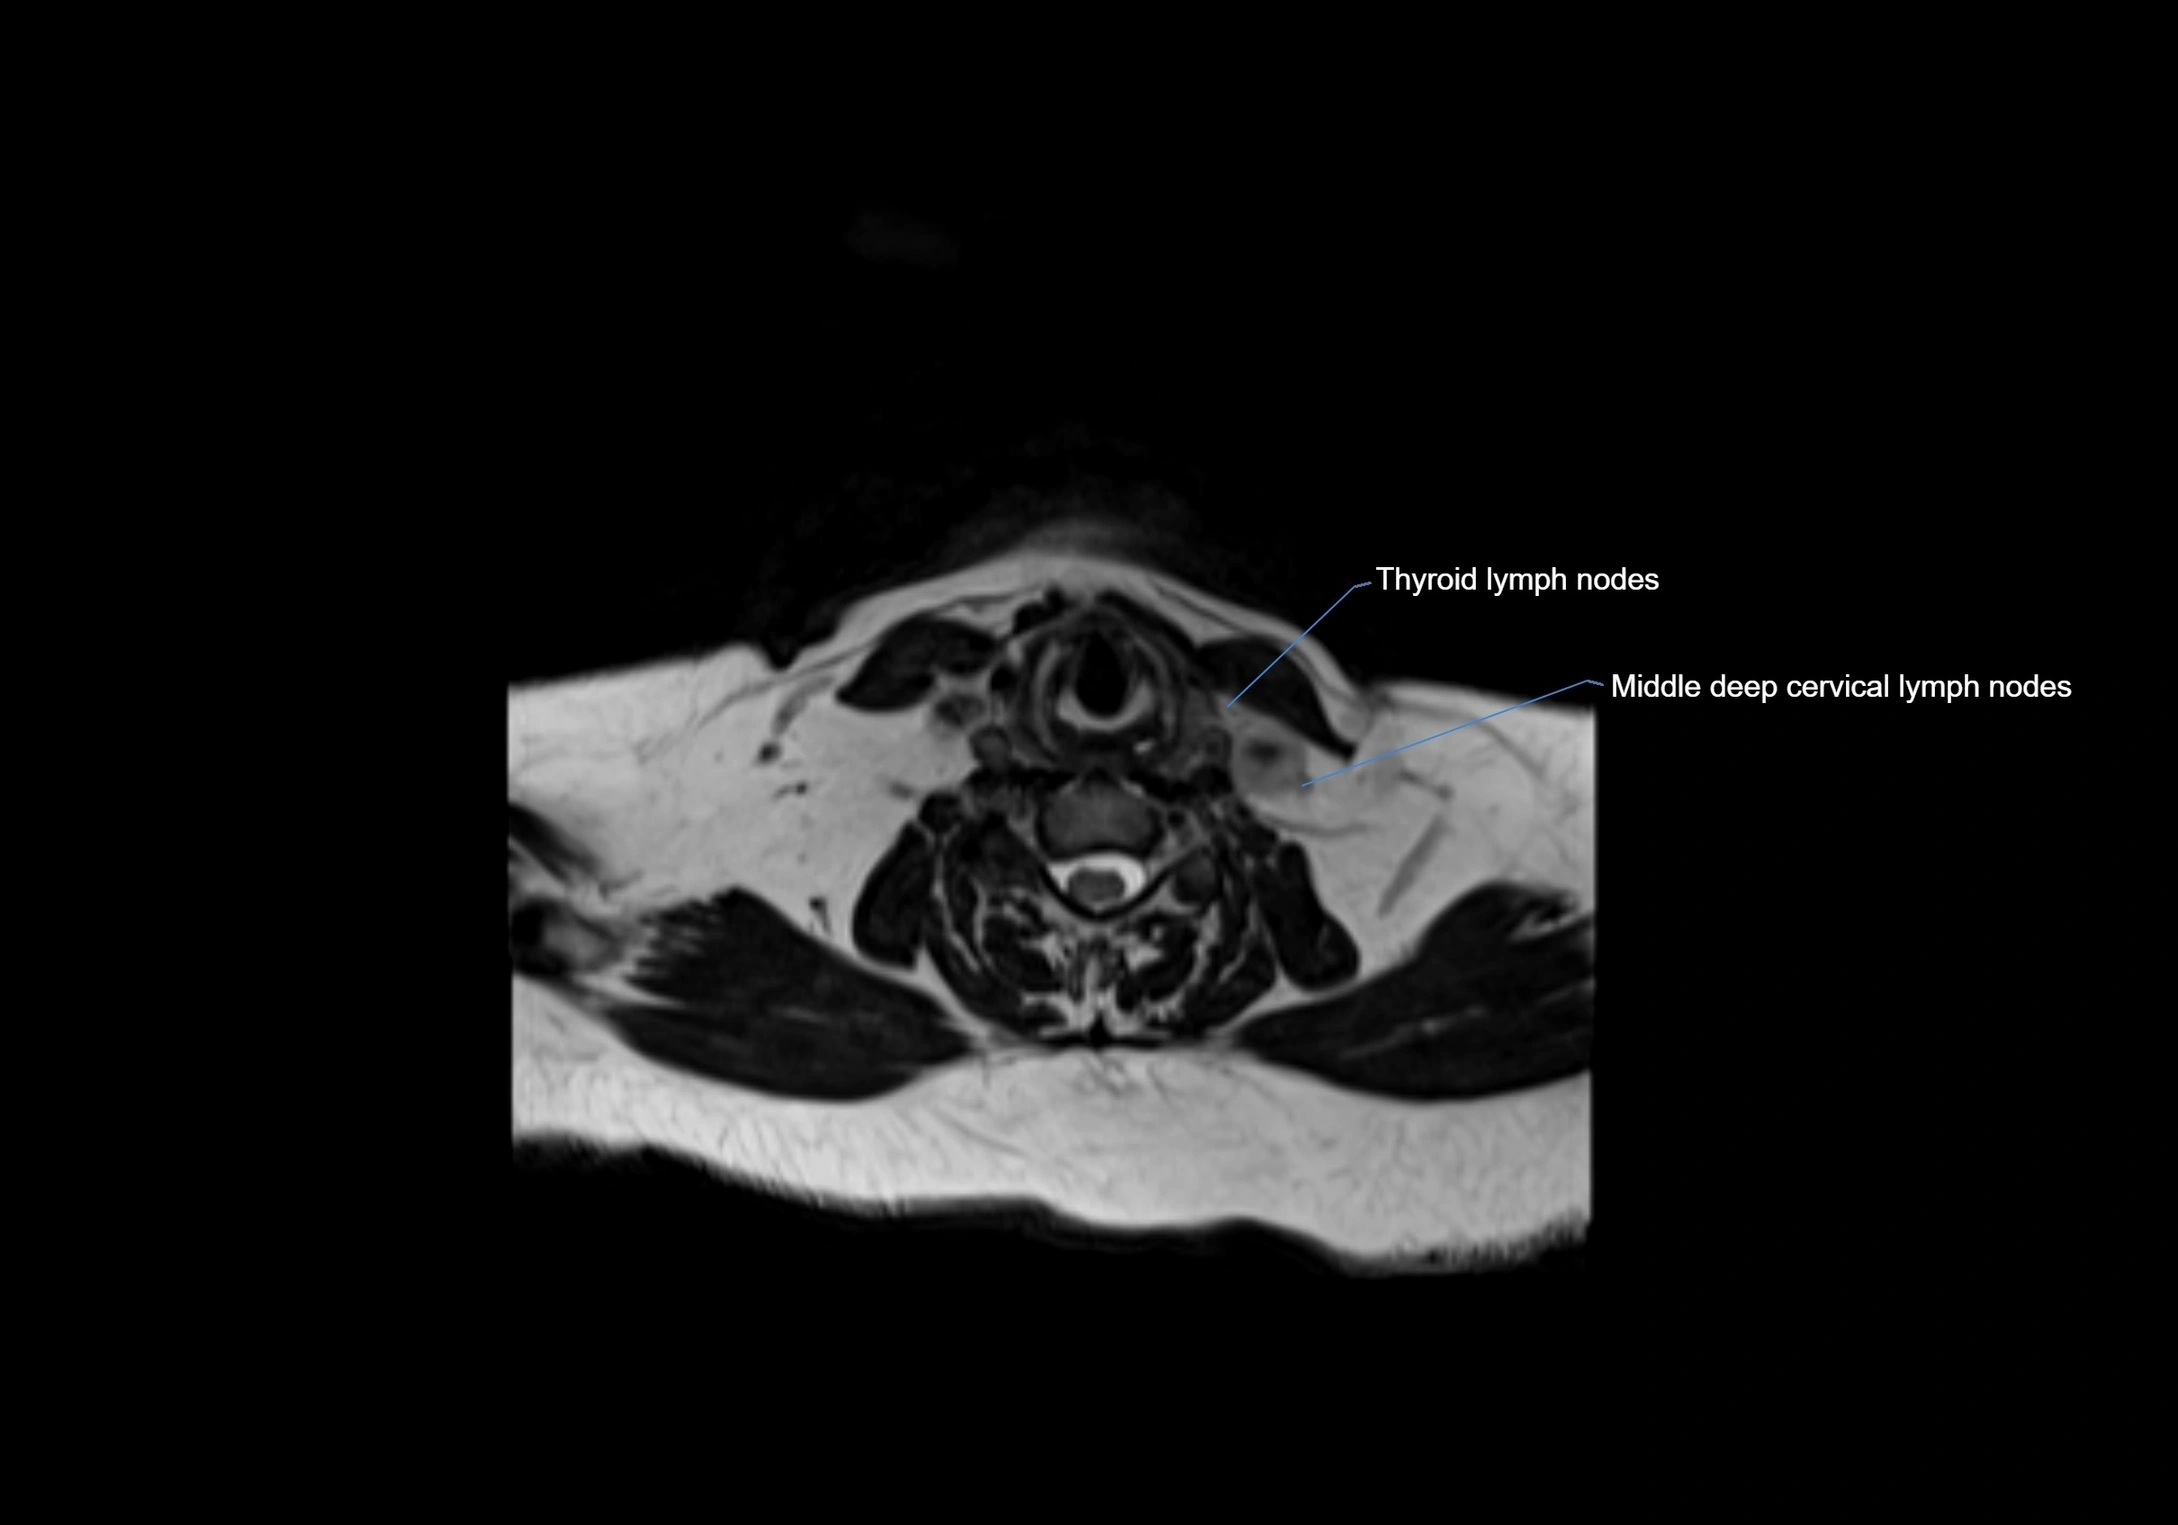

MRI Appearance

T1-weighted images:

• Normal accessory nodes appear as small, oval hypointense to intermediate signal structures within subcutaneous fat

• Surrounded by hyperintense fat, enhancing contrast for visualization

• Pathological nodes may appear enlarged or rounded, sometimes with cortical thickening

T2-weighted images:

• Nodes show intermediate signal, with surrounding fat bright

• Useful for detecting edema, inflammation, or infiltration

• Fatty hilum may appear slightly hyperintense relative to cortex

image